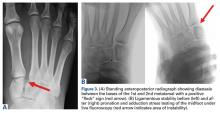

It is critical to obtain comparison weight-bearing radiographs of both feet during initial work-up to look for evidence of instability. Subtle radiographic findings of Lisfranc injury include a bony “fleck” sign, compression fracture of the cuboid, and diastasis between the base of the 1st and 2nd metatarsals and/or medial and middle cuneiforms (Figures 3A, 3B).

Stress testing involves pronation and adduction of the foot under live fluoroscopy to evaluate for diastasis. MRI can be helpful in cases of vague pain with negative radiographs and subtle displacement. Nonoperative treatment for cases of no instability or displacement involved protected weight-bearing for 4 weeks followed by progressive increase in activities, with RTP 6 to 8 weeks after injury.The goal of surgical intervention is to obtain and maintain anatomic reduction of all unstable joints in order to restore a normal foot posture. One of the difficulties with Lisfranc injuries is that there are no exact diastasis parameters and individuals should be treated based on symptoms, functional needs, and degree of instability. It has been shown that 5 mm of displacement can have good long-term clinical results in select cases without surgery.18 For surgery, we recommend open reduction to remove interposed soft tissue debris and directly assess the articular surfaces (Figures 4A-4D).